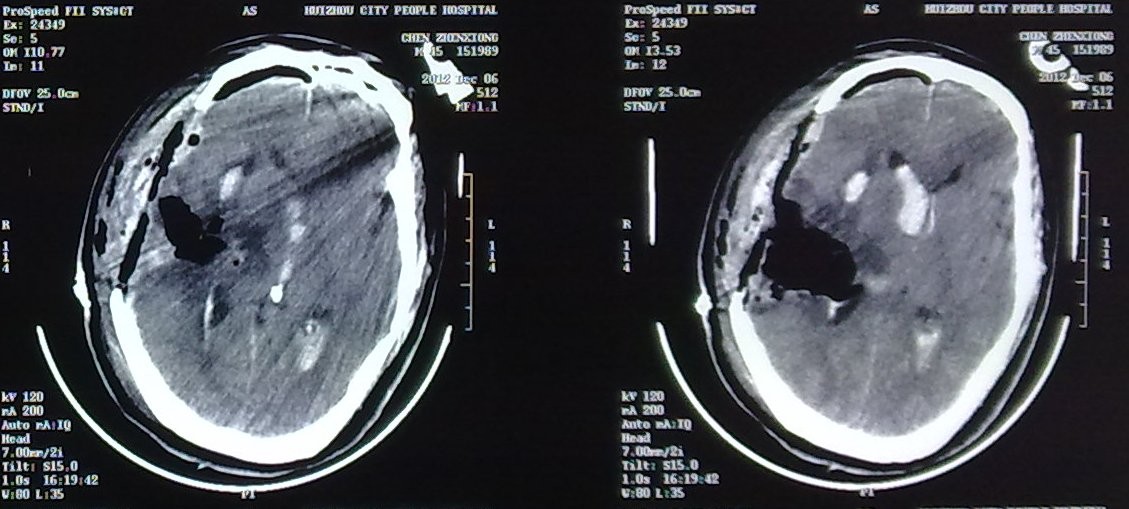

這是一位44歲的男性患者,因突發(fā)不省人事1小時急診入院,初步診斷可能是右顳頂腦內(nèi)血腫并腦疝、右顳頂動靜脈畸形。因為腦疝形成需要急診手術(shù),術(shù)前無法作進(jìn)一步檢查來明確出血的原因,為了安全,第一次只作血腫大部分清除術(shù),使腦疝緩解,瞳孔回縮,并不冒險深入探查。但是術(shù)后不久瞳孔又再次散大,復(fù)查頭顱CT提示再出血,出血量超過第一次,約100多毫升,廣泛占據(jù)大半個腦組織,形成巨大腦內(nèi)血腫并腦室鑄型血腫,深昏迷,瀕死狀態(tài),若在以往該患者必死無疑。

1、巨大腦內(nèi)血腫并腦室鑄血腫